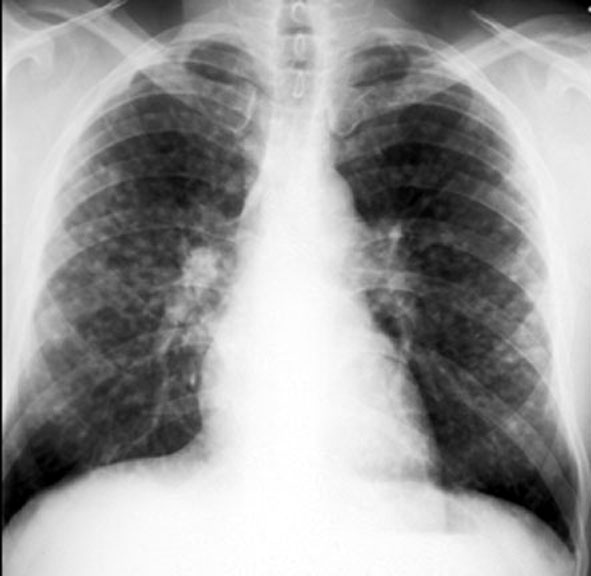

Sarcoidosis / Miliary Nodules / Hilar Nodes